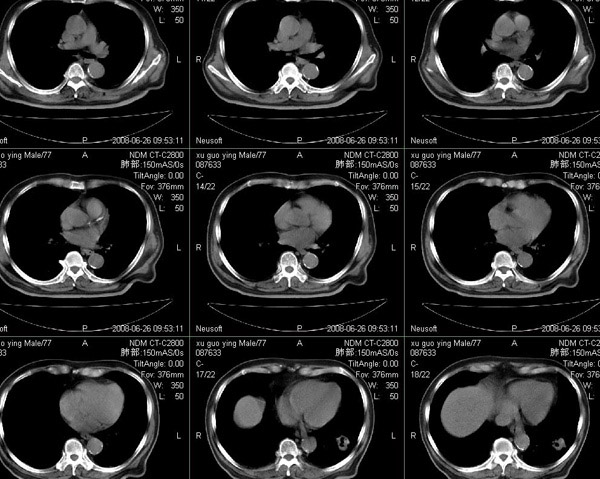

以下是引用狙击手在2008-6-26 20:16:00的发言:[br]上腹部除了胆囊大一点,其余未见明显异常,肺尖部见纤维条索样影,左肺下叶见空洞样占位,壁较厚,临近胸膜见牵拉,周围未见卫星灶,考虑:1:左下肺周围性肺癌;2:肺尖部陈旧性结合灶。

以下是引用liuqiang在2008-6-26 21:11:00的发言:[br]上腹部除了胆囊大一点,其余未见明显异常,肺尖部见纤维条索样影,左肺下叶见空洞样占位,壁较厚,临近胸膜见牵拉,周围未见卫星灶,考虑:1:左下肺周围性肺癌;2:肺尖部陈旧性j结核灶。